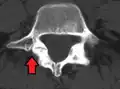

Computed tomography (CT)

Computed tomography can be helpful in evaluating bony vertebral abnormalities, such as fractures.[38] This can be helpful in determining if the fracture is a new, old, and/or progressing fracture.[38] CT use in spondylolisthesis evaluation is controversial due to high radiation exposure.[39]